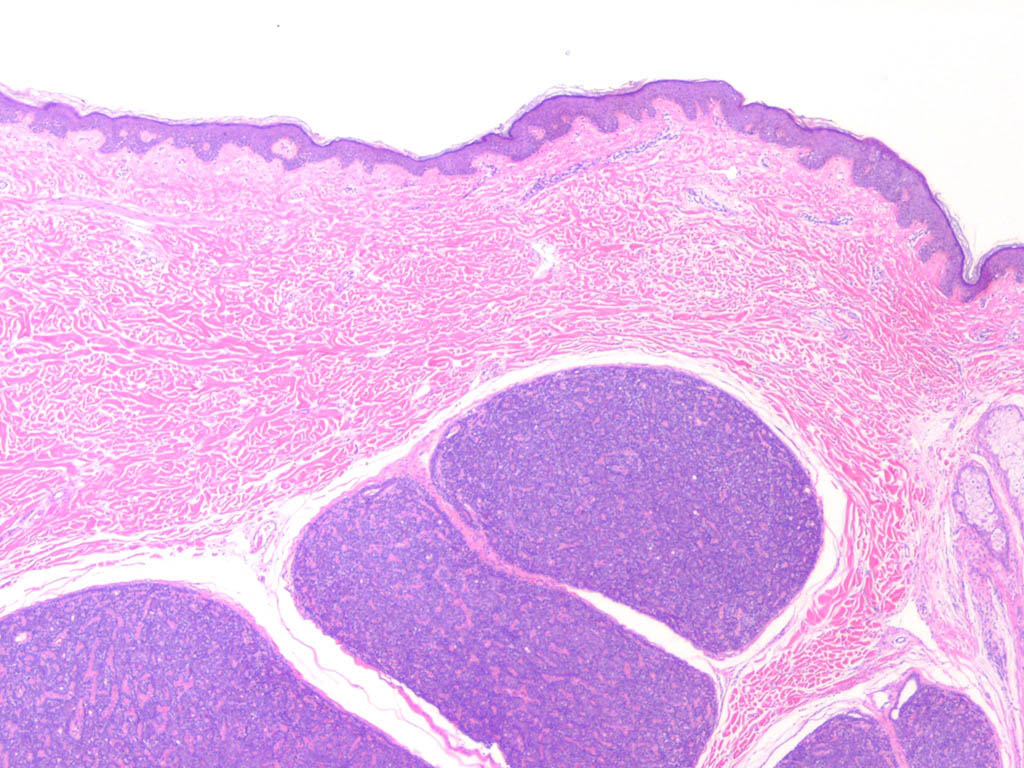

Spiradenoma=ورم غدي عرقي